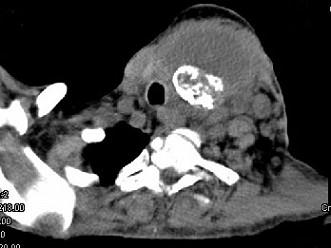

问题 女,64岁,发现双甲状腺肿大一月余,CT如图所示,最可能诊断为 ( )

选项 A、甲状腺转移癌 B、甲状腺结核 C、甲状腺腺瘤 D、甲状腺癌并淋巴结转移 E、结节性甲状腺肿

答案 D